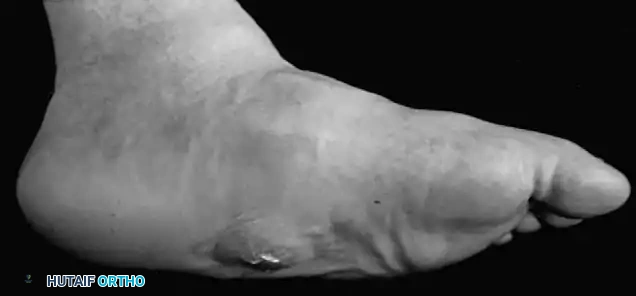

Diabetic ulcers predominantly occur in the forefoot, specifically beneath the metatarsal heads or the interphalangeal (IP) joint of the hallux.

Fig. 82-2 Stage III ulcer beneath second metatarsal head that extends into metatarsal head with presumptive contiguous osteomyelitis.

The pathogenesis is deeply rooted in biomechanical dysfunction. Fixed clawing of the toes, secondary to intrinsic muscle paralysis, forces the metatarsal heads plantarward. This is particularly devastating beneath the first metatarsal head, where the sesamoid bones lie just beneath the skin, creating massive shear forces during the terminal stance phase of gait.

In approximately 30% of patients with plantar forefoot ulcerations, atherosclerosis of the tibial and peroneal arteries significantly prolongs healing time. Recurrent infections and progressive deformities often necessitate multiple toe amputations or transmetatarsal amputations.